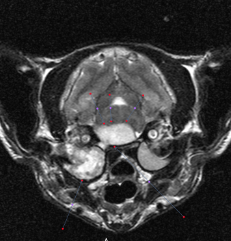

An MRI was performed that day, which showed several abnormalities, including severe chronic right-sided otitis media, interna, and externa, with intracranial extension resulting in a large intracranial extra-axial abscess and increased intracranial pressure.